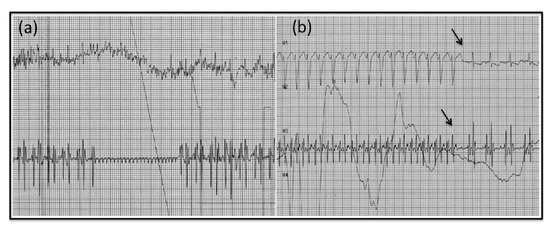

2. Case Report